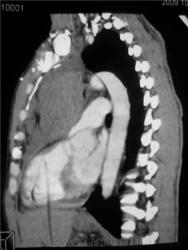

Мужчина 36 лет, рентгеногафия и КТ грудной полости.

Жалобы на субфебрильную температуру, боли в грудной клетке справа, слабость, похудание. ФГ 10 месяцев назад - норма.

КТ август 2009.

Интенсивное, однородное затемнение в средних отделах справа, слева норма - мною был заподозрен м/долевой плеврит, пациент был направлен в областной центр торакальной хирургии. Затем онкодиспансер, затем институт рака в Киеве. Результат гистологии тератобластома средостения. 2 курса химиотерапии контрольное КТ в октябре - отрицательная динамика.

Массивное неоднородное мягкотканное новообразование, исходящее из верхней или средней трети переднего средостения, оттесняет крупные сосуды вправо и кзади. По локализации должна быть злокачественная тимома. Хотя и лимфому наверное, не стоит отбрасывать, Ходжкинская маловероятна.